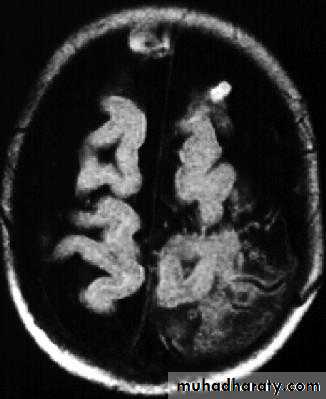

Brain Abscess MRI

Neurosurgery

• CT or MRI is the investigation of choice.

• CT Brain is performed with and without contrast.

• MRI is done with gadolinium enhancement.

• They will show a single (or multiple) space occupying lesion that is well delineated with an enhancing wall, with variable surrounding oedema.